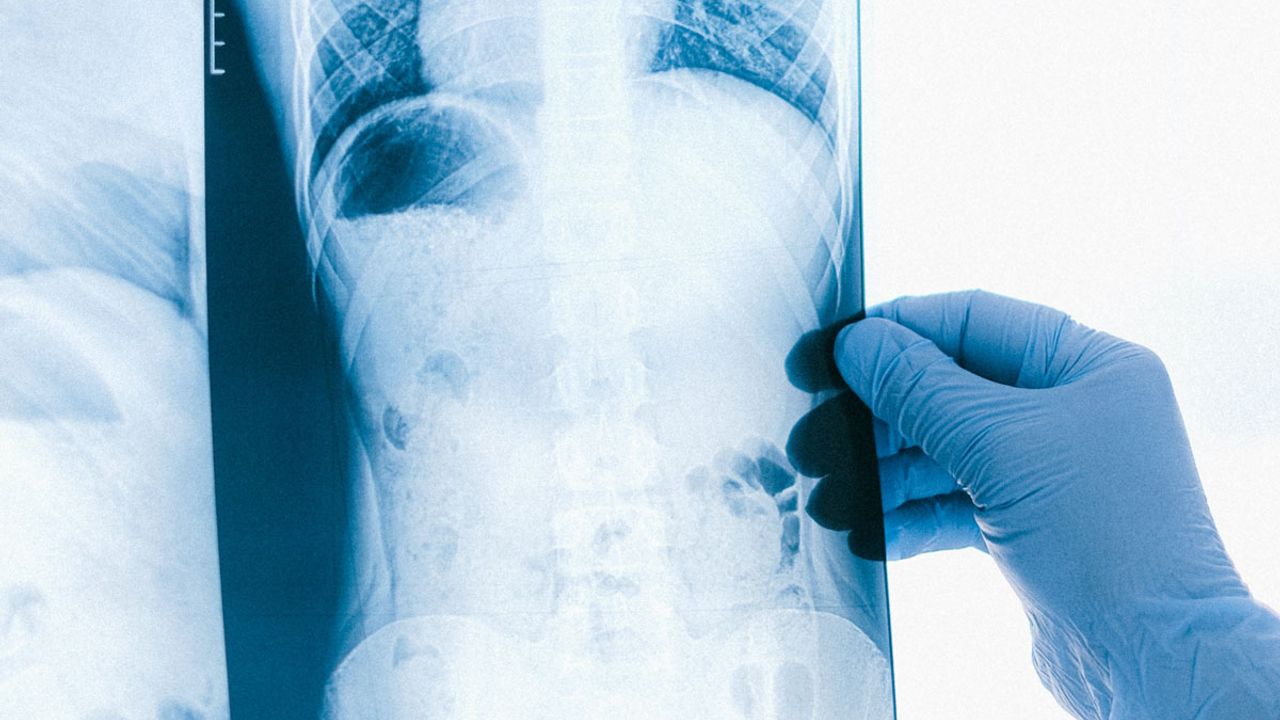

Niğde İl Sağlık Müdürlüğü, akciğer kanserinin erken belirtileri hakkında uyarılarda bulundu. Sağlık Müdürlüğü, vatandaşları şu belirtilere karşı dikkatli olmaya çağırdı:

Açıklamada, bu belirtilerin uzun süre devam etmesi durumunda vakit kaybetmeden bir sağlık kuruluşuna başvurulması gerektiği vurgulandı. Erken teşhisle tedavi şansının arttığına dikkat çeken İl Sağlık Müdürlüğü, vatandaşları bilinçli bir şekilde sağlık kontrollerini yapmaya teşvik etti.